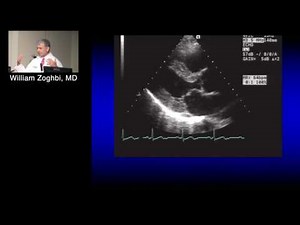

Cardiaque - Effet Doppler